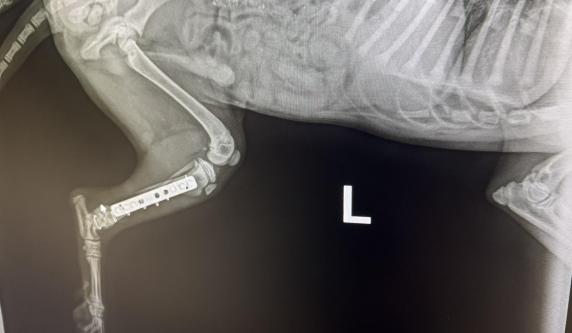

HUBSI 191035000271550 M, 3.1.2026., in the shelter since 18.3.2026., from street near Roma village where he was hit by a car and came with broken back leg. It was operated and he is recoevring very well in Alex's house. X-ray shots are in his album. He is vively, active, playful and happy puppy. He likes attention, and compan yof people and other dogs. At the moment cca 32 cm